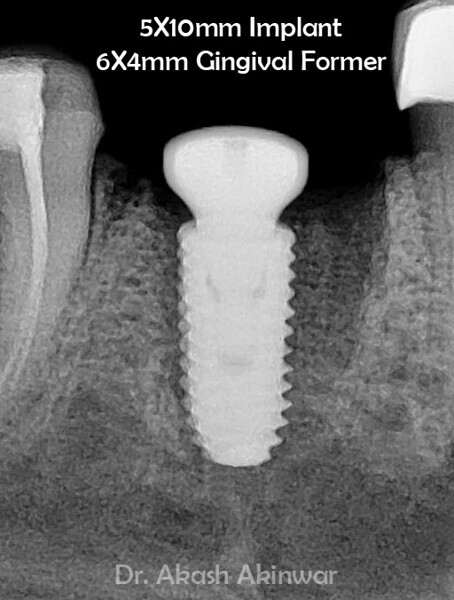

Flapless Single Implant Placement with Screw Retained PFM Prosthesis: Dr Akash Akinwar